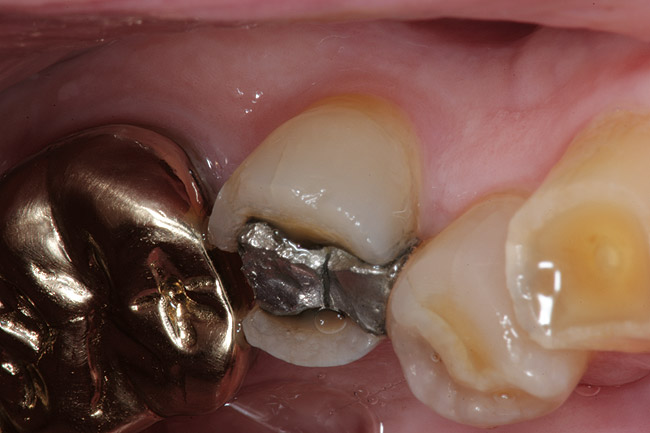

Replacement of existing restorations is responsible for 75% of all operative dentistry.15,19 The reasons for placement and replacement of restorations of direct restorative materials include: primary caries (Figure 1 and Figure 2); recurrent caries (Figure 3); poor margins (Figure 4 and Figure 5); restoration fracture (Figure 6 and Figure 7); tooth fracture (Figure 8); esthetics (Figure 9); non-carious tooth structure lost (attrition, abrasion, abfraction, erosion) (Figure 10); and pain/sensitivity.

Figure 3  Maxillary first molar with mesiobuccal tooth fracture and recurrent caries.

Figure 3

Figure 4  Defective margins. Mandibular first molar with an amalgam restoration with defective margins.

Figure 4